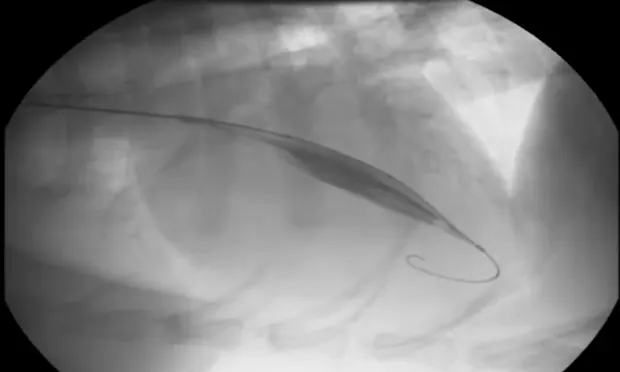

A catheter from the right carotid artery passing into the aortic root is used for angiography to identify the region of stenosis (arrow) and determine where to center the balloon. A cutting balloon is inflated in the stenotic region of the LVOT, scoring the tissue. A high pressure balloon is then inflated to open the stenotic region where it was previously scored.

Figure 1.

Right-sided 5-chamber long-axis view showing the left ventricular (LV) outflow tract. The LV is hypertrophied, and there is an obstructive ridge in the LV tract below the valve. (Ao = aorta; LA = left atrium)